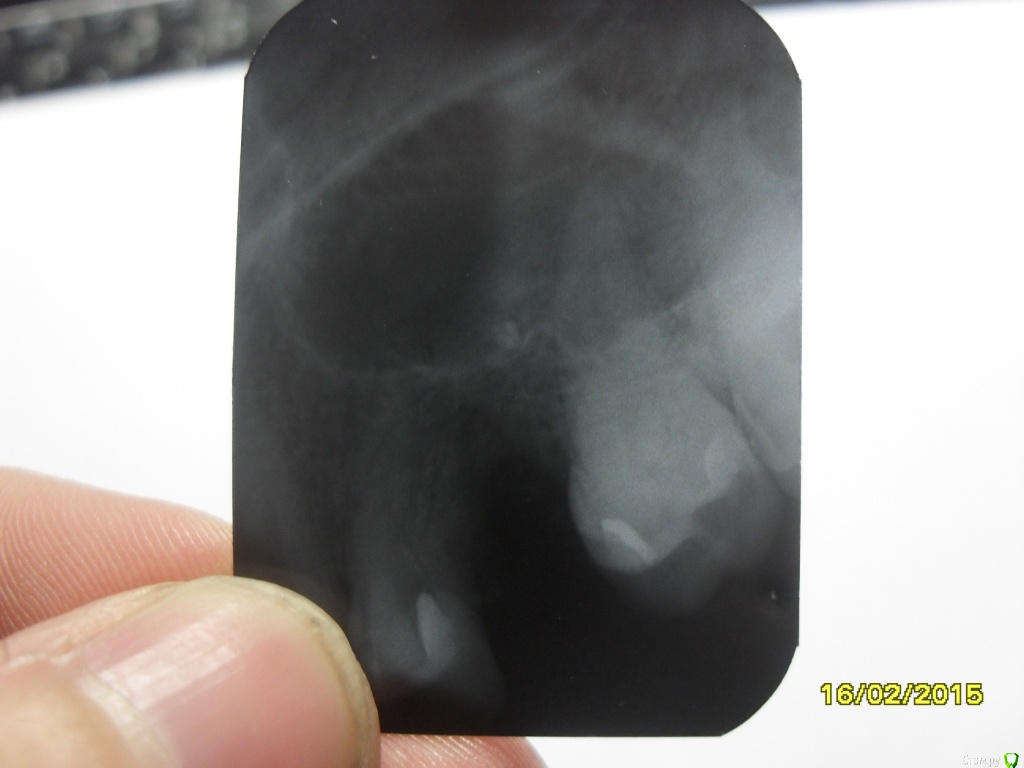

asin Опубликовано 16 февраля, 2015 Автор Поделиться Опубликовано 16 февраля, 2015 (изменено) надо дентальное КТ сделать, тогда будет ясно есть ли шанс перелечить зуб. Ну или сразу удалить.по рекомендации ЧЛХ удален зуб снимок прилагаю. я так понимаю пломб. мат остался.перфорация не нарушена. какую операцию рекомендуете Изменено 16 февраля, 2015 пользователем asin Ссылка на комментарий